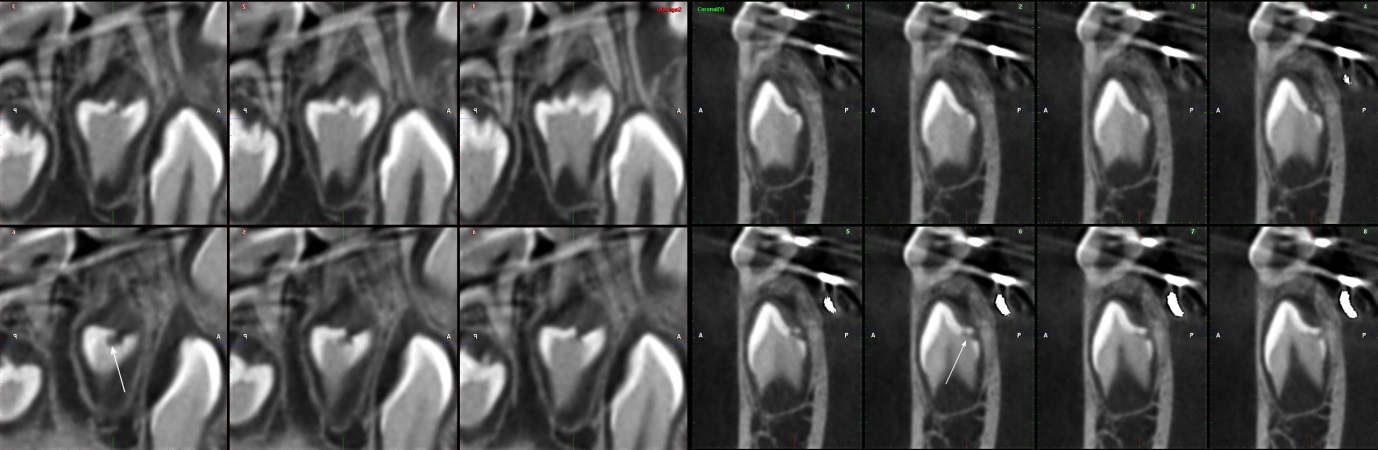

Se muestra la radiografía panorámica de una paciente femenina de 15 años de edad, en la que se observa la presencia de un defecto de RIPE de forma triangular bajo el esmalte de la cúspide distal de la pieza 38, de localización central y profundidad dentinal grado I (figura 6). En la THC adquirida, con un tamaño de vóxel de 0,2 mm, se observó un defecto dentinal de forma triangular y de grado I de profundidad, localizado en la cúspide distobucal, además de un defecto hipodenso del esmalte adyacente al defecto (figura 7).

Se tiene la radiografía panorámica de una paciente femenina de 45 años de edad, en la que se observa un defecto de RIPE en la pieza impactada 48, de localización mesial y profundidad dentinal de grado I, y, además, un segundo defecto ubicado en el centro de la corona y de forma alargada, que sería consistente con una fosa vestibular (figura 8). En la THC adquirida, con un tamaño de vóxel de 0,2 mm, se observó que el aparente defecto de RIPE mesial era, en realidad, la fosa mesiobucal y, además, se encontró un defecto de RIPE, grado I, en la cúspide distolingual asociada a un defecto hipodenso del esmalte adyacente al defecto (figuras 9, 10 y 11).

En el caso 4, se observó la coexistencia de un defecto de RIPE y una fosa vestibular profunda. Hemos notado que las lesiones de RIPE tienen un mayor componente horizontal, mientras que la fosa vestibular profunda tiene un mayor componente vertical; tales diferencias podrían ser de utilidad al momento del diagnóstico diferencial.